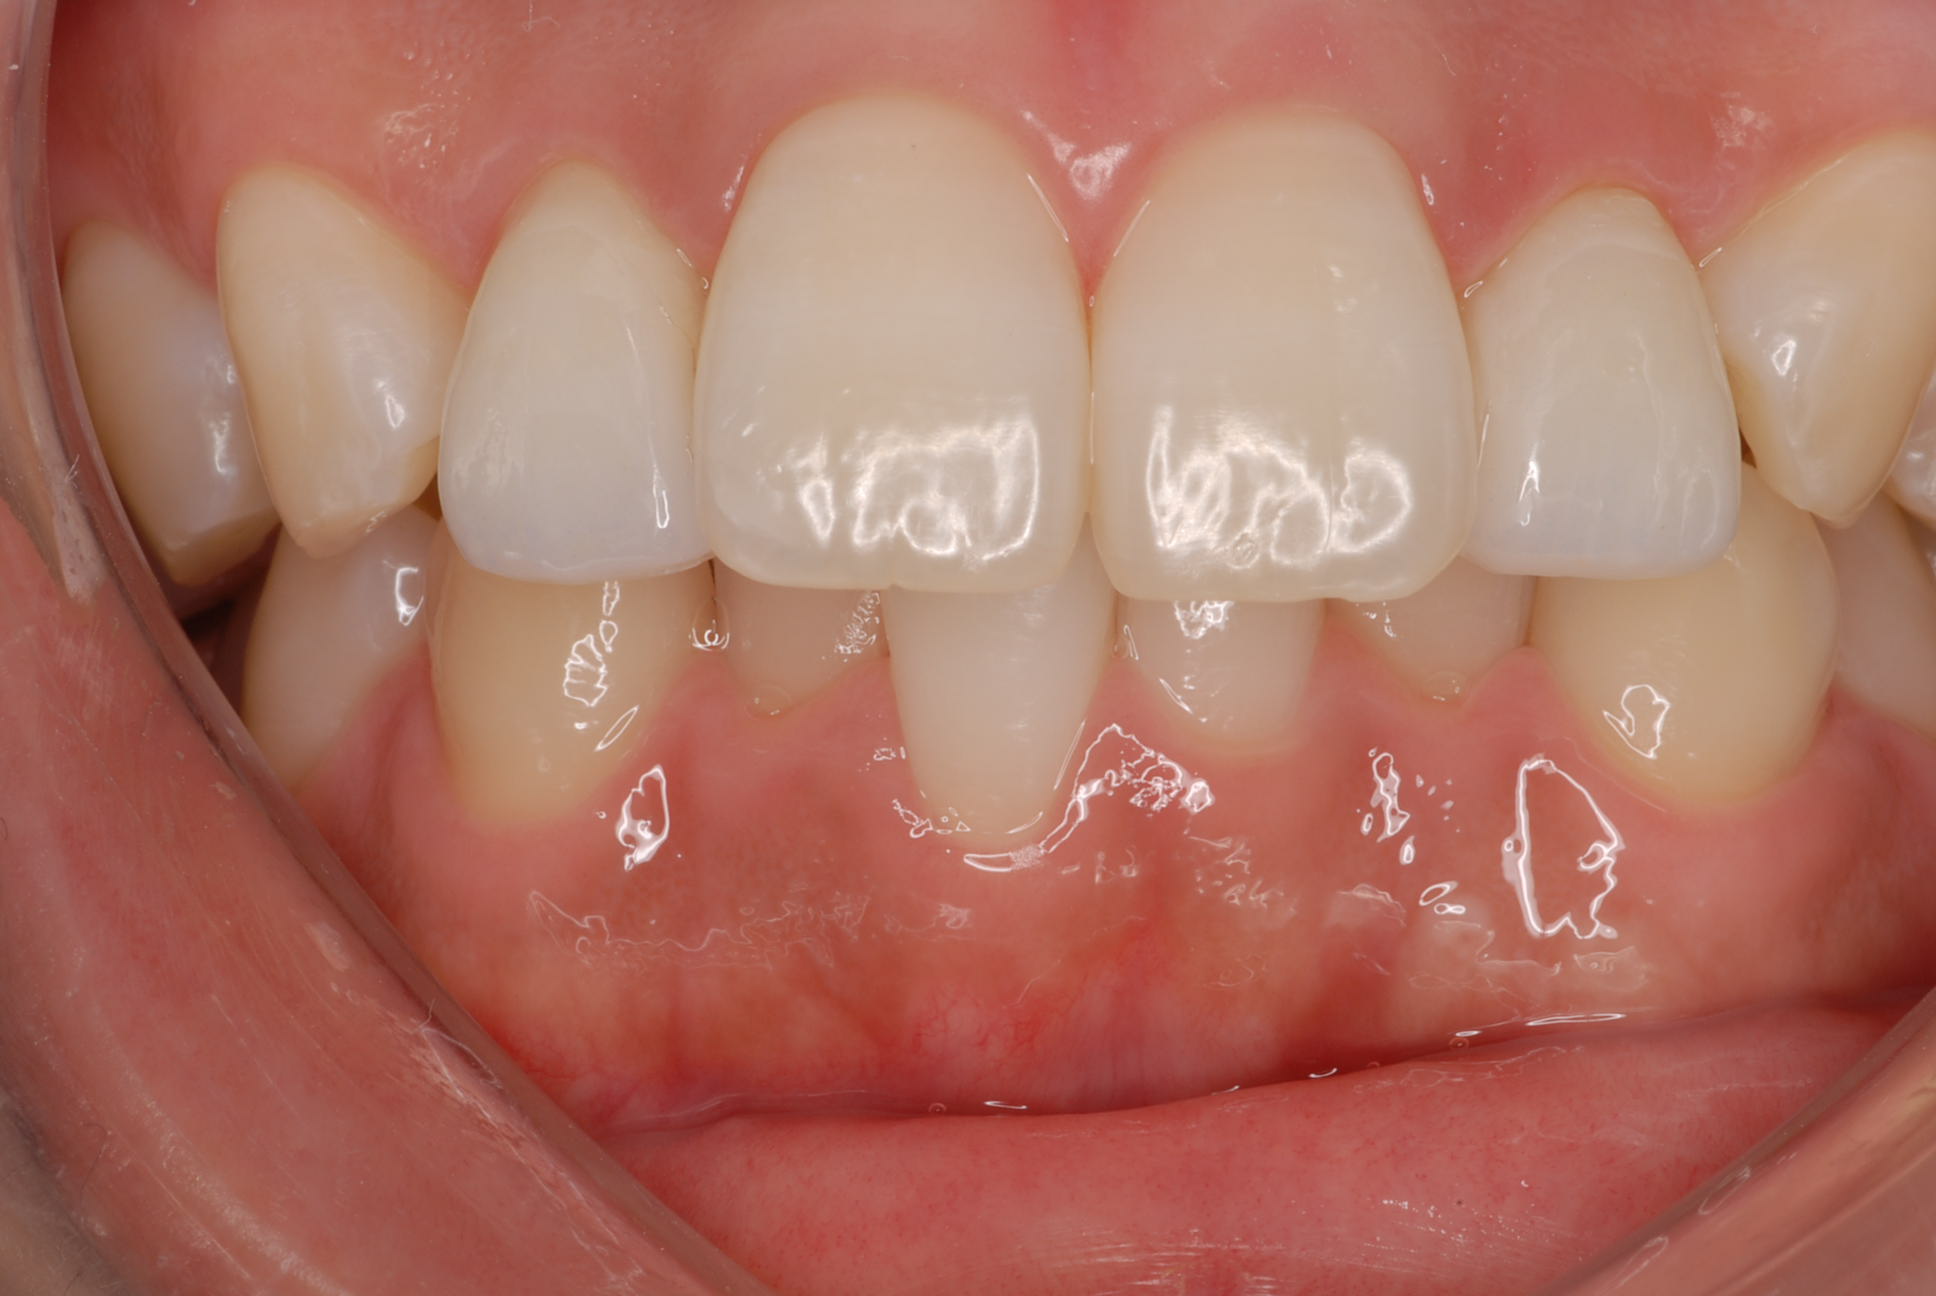

SET後

ラミネートベニアはもちろんセラミック。

e-MAXです。かなり強度があります。

われる心配がかなり減り,安心(^_^)

接着はリンクマスターで接着。